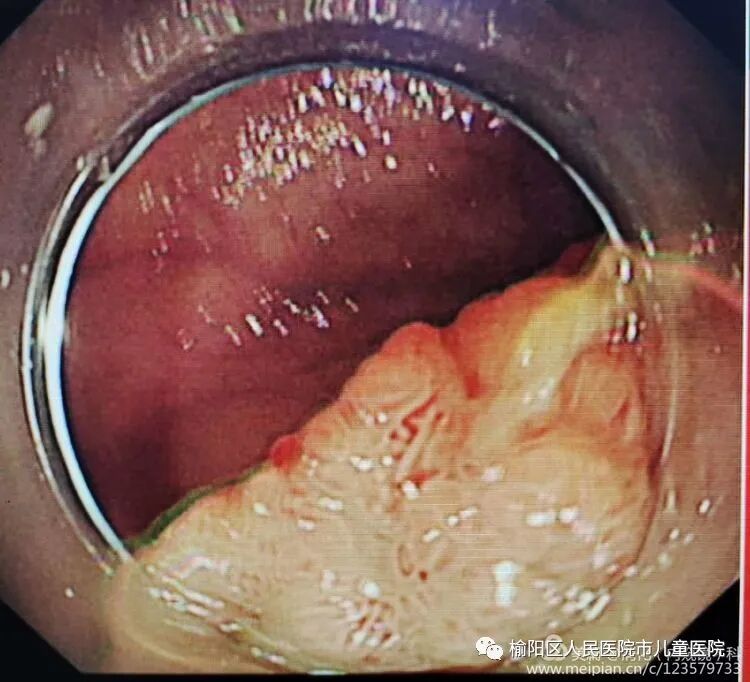

这就是内镜黏膜下剥离术ESD(endoscopic submucosal dissecfion)的整个过程。随着内镜微创技术的发展,越来越多的早期胃癌、肠癌、癌前病变及胃肠黏膜下疾病可完全在内镜下予以切除,免除了更大的手术创伤。

该治疗具有不改变消化道解剖结构、不开刀、体表无创口、创伤小、出血少、恢复快等优势,是近年来国际、国内最新兴起的内窥镜下微创治疗手段之一,适用于食管、胃、十二指肠等上消化道及结、直肠的黏膜下良性肿瘤、黏膜的早期癌变以及具有癌变倾向病变的切除治疗。